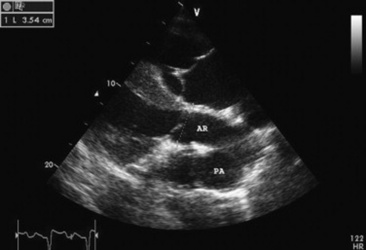

Echocardiography is the diagnostic technique of choice for identifying a VSD. With two-dimensional echocardiography the VSD can be imaged directly (Fig. 30-5) and the shunt size, location, and direction demonstrated with pulsed wave Doppler, continuous wave Doppler, color flow echocardiography, or the injection of microbubbles. Careful scanning of the interventricular septum should be performed with two-dimensional echocardiography to directly image the VSD and measure its maximal diameter in two mutually perpendicular planes.31,32 The typical membranous VSD (≤2.5 cm in both planes) is missed if the long-axis view of the left ventricular outflow tract is not examined. The membranous VSD is located underneath the septal leaflet of the tricuspid valve and the right or noncoronary leaflet of the aortic valve. If a membranous defect is not found, the entire septum should be carefully scanned in all imaging planes to detect the VSD. The subpulmonic location, more common in calves, is easy to miss. This defect is usually best imaged in the short-axis view, scanning the interventricular septum between the left and right ventricular outflow tracts. With a left-to-right shunt a high-velocity turbulent jet is depicted from the right parasternal window, originating in the left ventricle, traversing through the hole in the interventricular septum into the right ventricle with color flow Doppler echocardiography (blood flow toward the transducer), whereas a negative contrast jet is imaged in the right ventricle with a right-sided injection of microbubbles.31,32 A left ventricular injection of microbubbles is necessary to visualize echo-laden blood in the right ventricle with a typical VSD. M-mode echocardiography may show septal discontinuity when traversing the ventricular septum from the apex of the heart to the aortic root (septal dropout). Moderate to large VSDs show left atrial and left ventricular enlargement, right ventricular enlargement, and pulmonary artery dilation. The left atrial—to—aortic root ratio is increased. Aortic valve prolapse and aortic regurgitation may also be detected because of loss of support of the aortic root from the VSD. Myocardial dysfunction and subsequent CHF may occur with a large VSD. Continuous wave Doppler echocardiography can be used to noninvasively assess the hemodynamic significance of the shunt (see Fig. 30-5, B). A peak shunt flow velocity of greater than or equal to 4 m/sec indicates a restrictive VSD with normal or near normal right ventricular pressures. Nuclear angiocardiography can also be used to demonstrate simultaneous opacification of the left and right ventricles. The radiographic presence of cardiomegaly and increased vascularization of the lungs provides only nonspecific evidence of VSD. If polycythemia is found, a complicated VSD should be suspected.

image

Fig. 30-5 Two-dimensional echocardiographic image (A) and continuous wave Doppler spectral tracing (B) of a ventricular septal defect (arrow) in a weanling colt. The ventricular septal defect (VSD) is located just underneath the septal leaflet of the tricuspid valve and right coronary cusp of the aortic valve. The VSD is best imaged in this left ventricular outflow tract view. There is significant left ventricular enlargement in this colt. The right atrium (RA), right ventricle (RV), left ventricle (LV), left atrium (LA), aortic root (AR), and pulmonary artery (PA) are all visible in this view. The spectral tracing shows a peak shunt velocity of slightly under 4 m/sec in systole, with some turbulent flow (spectral broadening) also detected in diastole with a peak flow velocity of approximately 1.3 m/sec.